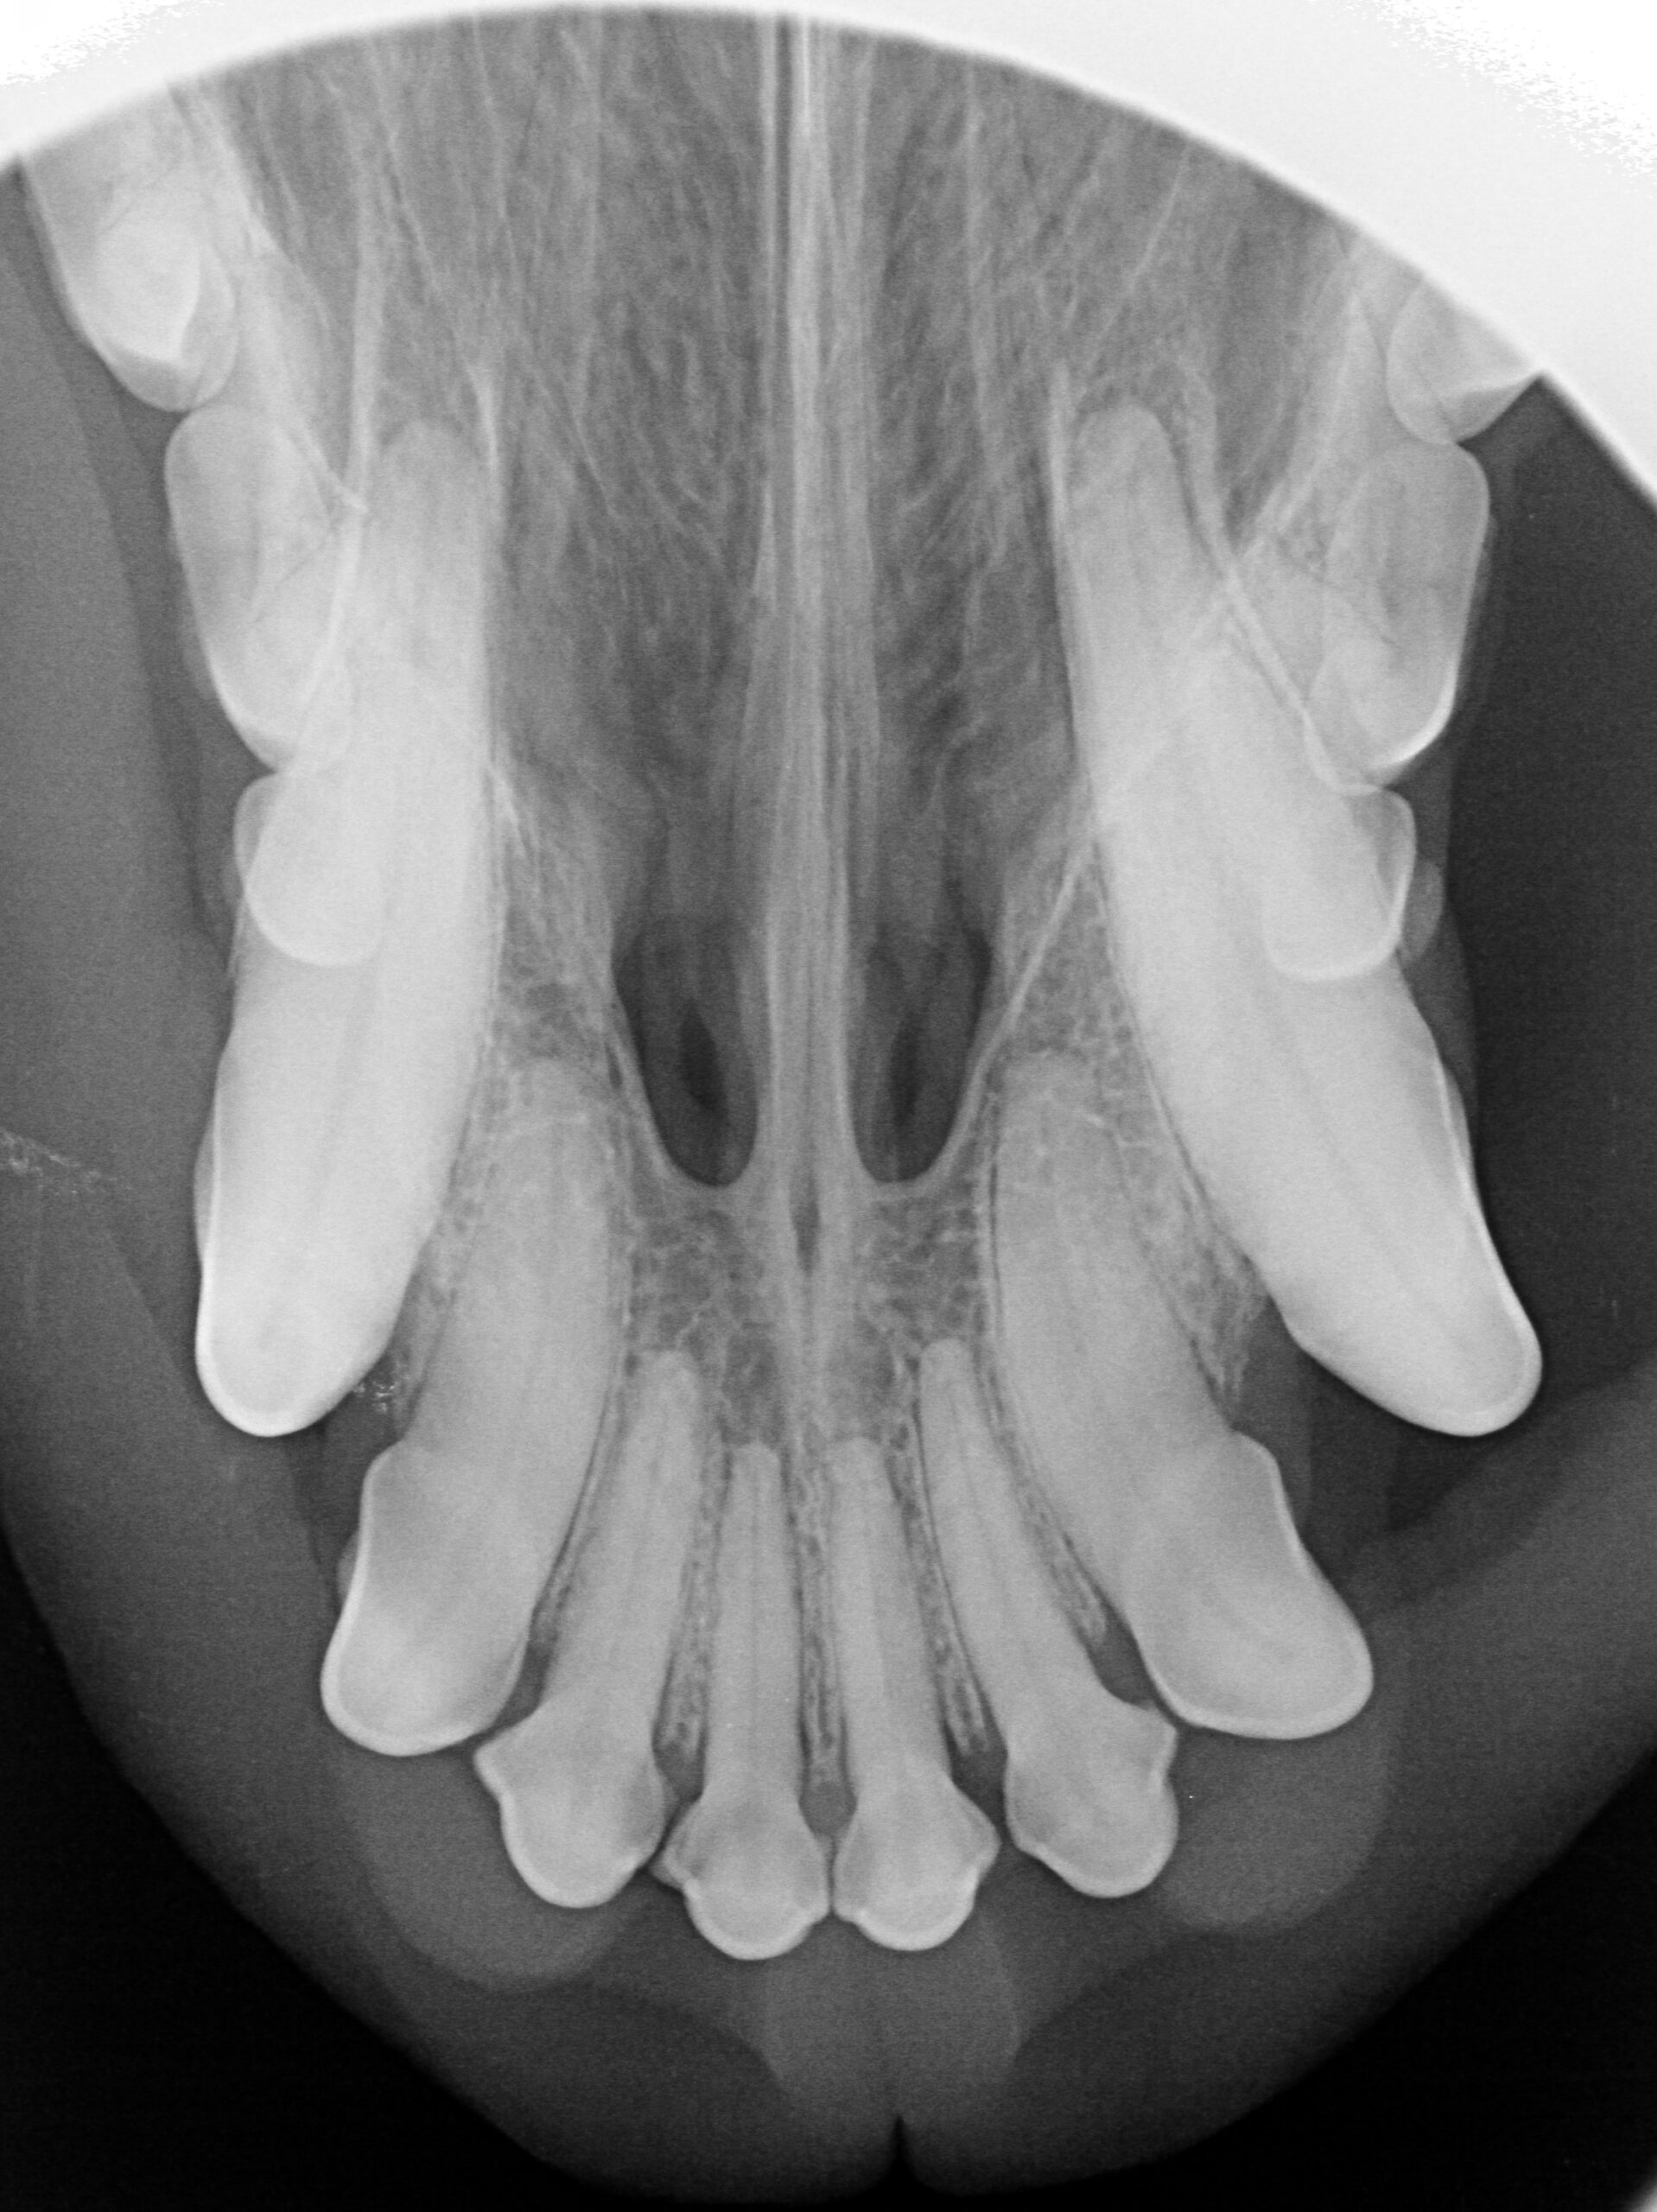

ZAHNRÖNTGEN

Seit Anfang 2025 zählt neben einer Zahnstation auch ein hochmodernes Zahnröntgen zu unserer Praxisausstattung. Mit dieser Technik können wir präzise Aufnahmen der Zähne und des Kiefers anfertigen, um verborgene Probleme zu erkennen, die mit bloßem Auge nicht sichtbar sind. Das ermöglicht eine umfassende und schonende Zahnbehandlung, die gezielt auf die Bedürfnisse Ihres Tieres abgestimmt ist.

Wir bieten Zahnsteinentfernung/Zahnsanierung mit oder ohne Zahnextraktion an. Nach der Reinigung werden die Zähne poliert. Dazu wird Polierpaste auf einen rotierenden Gummi aufgetragen. Das Polieren glättet die Zahnoberfläche, wodurch Bakterien weniger gut anhaften können.

Gesunde Zähne tragen maßgeblich zum Wohlbefinden und zur Lebensqualität Ihres Vierbeiners bei. Gerne beraten wir Sie ausführlich zur Zahngesundheit.